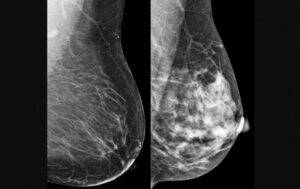

O câncer de mama foi escolhido como alvo para teste do modelo computacional porque é o tipo mais comum entre mulheres no mundo, com 2,3 milhões de casos e 670 mil mortes registradas em 2022 (imagem: CDC/reprodução)

O câncer de mama foi escolhido como alvo para teste do modelo computacional porque é o tipo mais comum entre mulheres no mundo, com 2,3 milhões de casos e 670 mil mortes registradas em 2022. A detecção precoce é crucial para aumentar as chances de cura e sobrevida. No entanto, métodos tradicionais, como a mamografia, dependem fortemente da interpretação humana, o que pode levar a variações no diagnóstico. “Apesar de ser teoricamente simples de acompanhar, a mamografia ainda é um exame cuja interpretação depende muito do profissional que realiza o procedimento”, diz Papa.